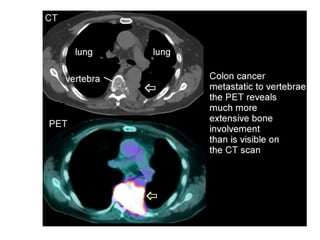

MRI

BONE SCAN

PET SCAN